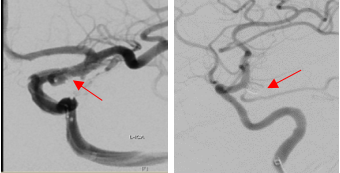

头颅CT显示左侧基底池及侧裂血量较对侧多;头CTA断层可清楚显示右侧后交通段动脉瘤

LIVS支架辅助栓塞后造影显示微小动脉瘤不显影,分支通畅;双微管栓塞后显示右侧后交通段动脉瘤不显影,分支通畅